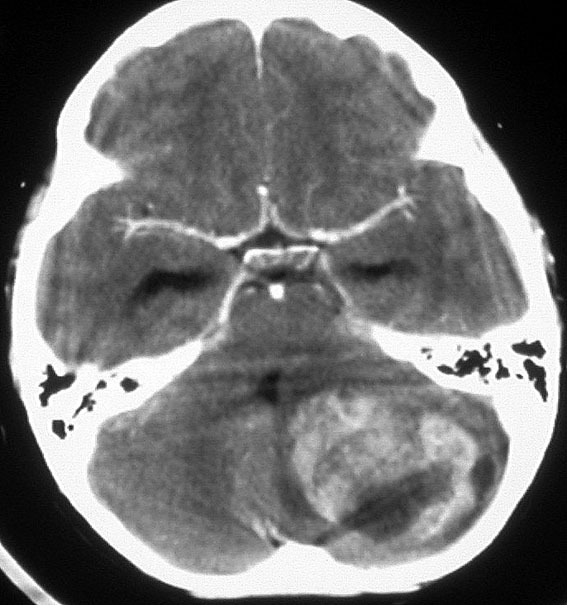

この例は,小脳半球にできたものです。のう胞(水たまり)を形成しています。髄芽腫の大きな特徴は,造影剤を入れないCT(左側)で腫瘍が少し白く見えることです(灰白質より高密度といいます)。細胞密度が高いので高密度になります。この例はclassic medulloblastomaですが,MIB-1は45%に達するもので,急激な腫瘍発育を示します。